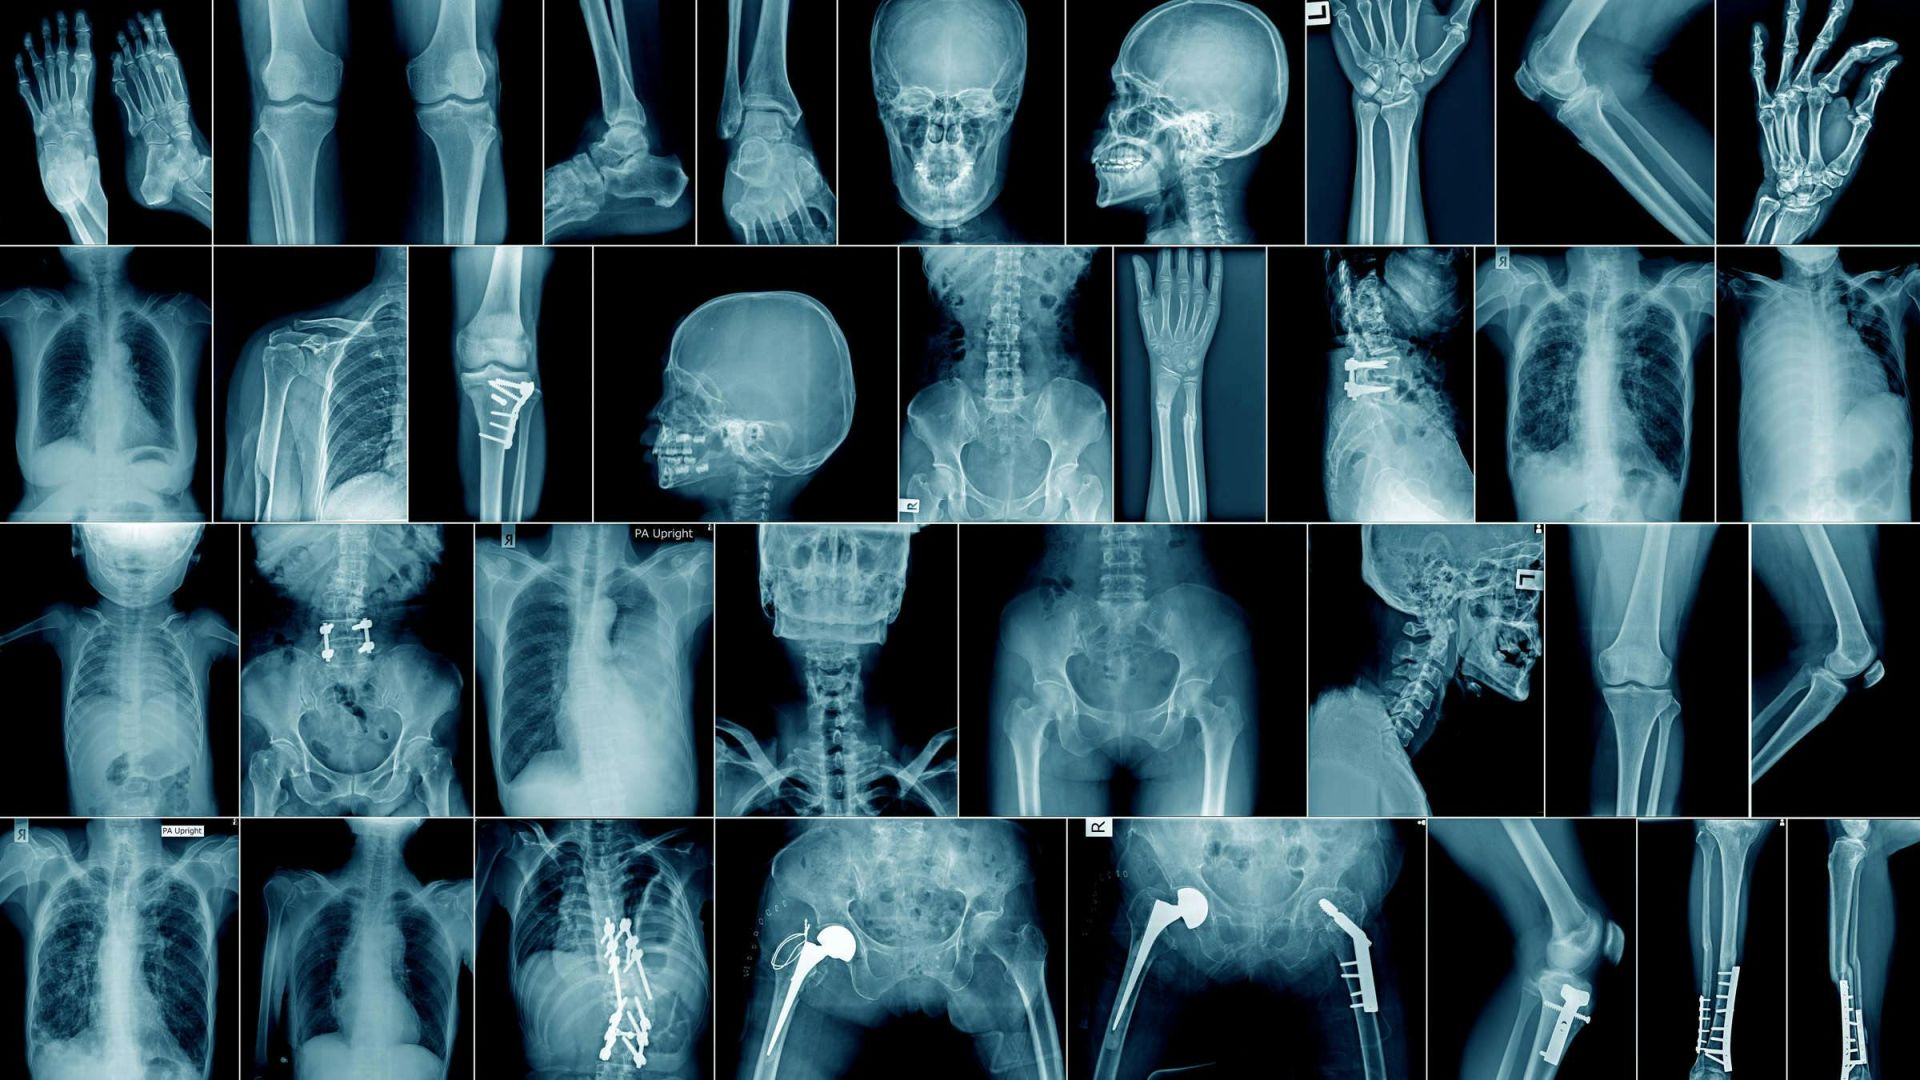

Der Fall steht exemplarisch für ein größeres Problem. Inzwischen sind mehr als 1.300 KI-gestützte Medizinprodukte von der FDA zugelassen – doppelt so viele wie noch vor wenigen Jahren. Darunter finden sich Herzmonitore, Ultraschallgeräte und Bildanalyse-Software.

Auch bei anderen Herstellern häufen sich Meldungen. So wurde bei KI-unterstützten Herzmonitoren von Medtronic** berichtet, dass gefährliche Herzrhythmusstörungen nicht erkannt wurden. In einem anderen Fall meldeten Anwender, eine KI-Software für pränatale Ultraschalldiagnostik habe Körperteile von Föten falsch zugeordnet. Die betroffene Technologie stammt von Samsung Medison**, einer Tochter des Samsung-Konzerns.